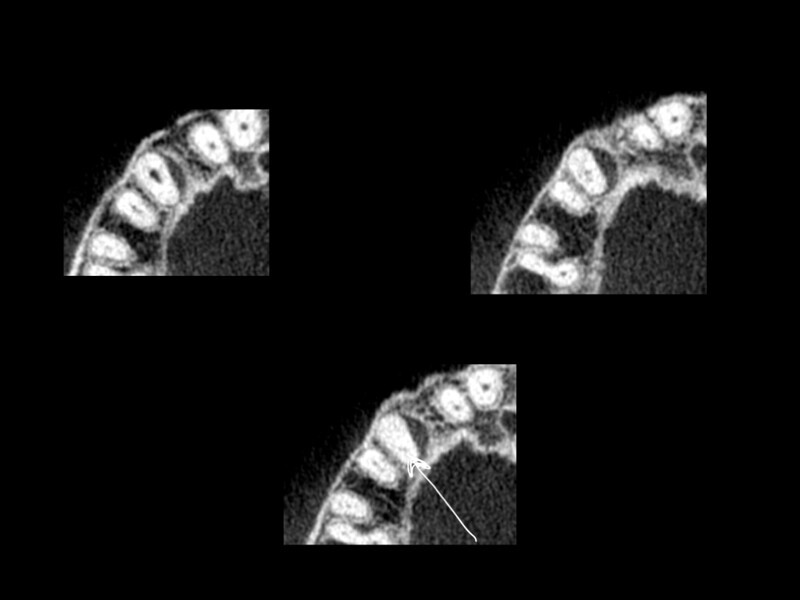

Treatment of the result of chronic activation of substance P